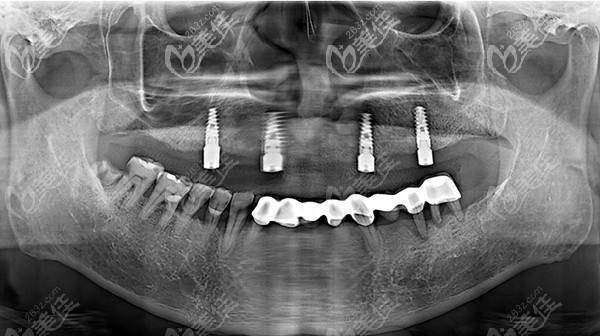

种植牙植入后

上半口牙种植需要种几颗?12—14颗就可以了

半口种植不需要为每一颗牙齿都植入种植体,我爸做的是allon4,也就是只需要4颗种植体的种植牙技术,便可以进行半口牙(12-14颗牙齿)的种植。

重要的是,半口种植能恢复12-14颗牙齿功能,但是收费却仅收4颗种植体的费用,对于缺牙的患者来言还是很实惠的。

既然说到了价格,就跟大家汇报一下,我爸种植的半口牙,用的是韩国登腾,总体下来三万多,据说可以使用二、三十年呢,还是比较划算的。现在我爸又恢复了吃嘛嘛香的状态,真好。